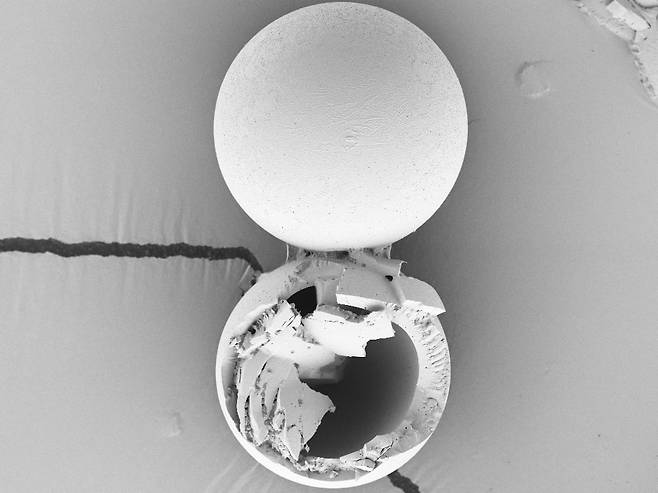

연구진은 한 번의 접종으로 추가 면역 효과까지 낼 수 있는 백신 플랫폼을 개발했다. 핵심 기술은 생분해성 고분자 물질인 PLGA로 만든 마이크로 캡슐에 백신을 담는 것이다. 백신을 접종할 때 마이크로 캡슐을 함께 주입하면 1차로 주사한 백신이 면역반응을 유발하고, 정해진 시간이 지나면 캡슐이 백신을 추가로 방출해 2차 접종 효과를 낸다.

새로운 백신 플랫폼은 냉장 보관에도 적합하다. 연구진은 섭씨 4도에서 4~7주 동안 냉장 보관하고 효과를 측정했다. 그 결과 면역 효과가 냉장 보관 이후에도 유지되는 것으로 나타났다. 마이크로 캡슐은 직경이 65㎛(마이크로미터·1㎛은 100만 분의 1m)로 일반 주사 바늘로도 주입할 수 있다.